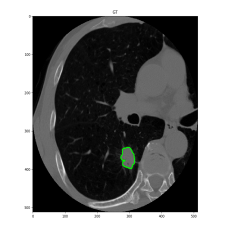

We argue that the sub-optimal paradigm of processing different abstractions within a single CNN pipeline can be remedied through the effective processing of information in a structured manner. Consequently, we devise strategies for disentangling the edge and texture information within a single training pipeline. Figure 2 illustrates how our proposed module, dubbed EG-CNN, can be paired with any existing CNN encoder-decoder to improve segmentation quality near intensity edges. We have applied our EG-CNN to the tasks of brain and liver tumor segmentation in medical images (Figure 3).

(1) Brain MR (2) Liver MR (3) Liver CT (4) Lung CT